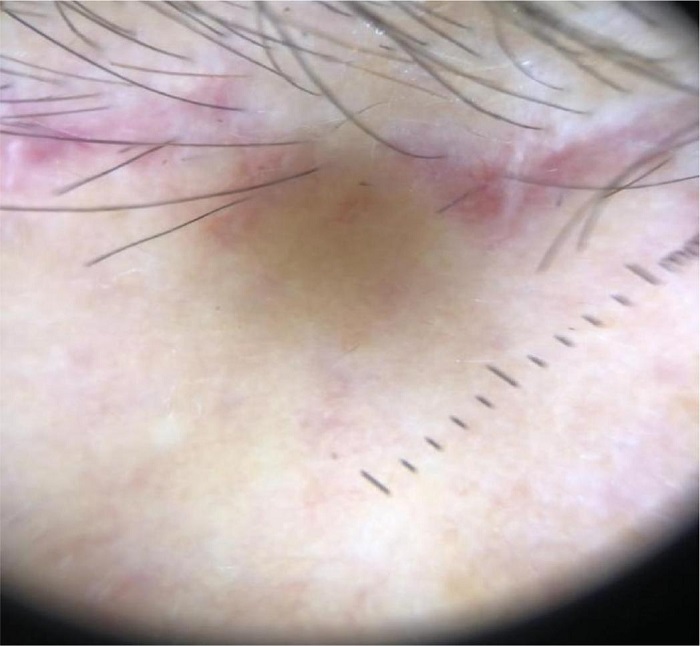

Com o paciente sentado, realiza-se a marcação da incisão. Delimita-se a região de máxima elevação no terço lateral com uma linha de concavidade superior inferiormente à sobrancelha, onde será realizado o descolamento no plano subcutâneo. Na região medial, onde se localizam os nervos supraorbital e supratroclear, demarca-se uma linha de concavidade inferior, acima da sobrancelha, que será o limite inferior do descolamento, com o objetivo de reduzir o risco de lesão nervosa e evitar a elevação excessiva da porção medial das sobrancelhas. Na região da glabela, marca-se uma linha de concavidade superior, que servirá de ponto de referência para o limite inferior do descolamento (Figura 1). Os limites laterais são marcados com uma linha vertical traçada na altura da crista temporal. A incisão superior é demarcada cerca de 5 mm posteriormente à linha de implantação frontal do couro cabeludo, apresentando um desenho irregular que simula o formato da linha de implantação natural (Figura 2). Realiza-se anestesia local tumescente com injeção de uma solução anestésica constituída por 80 mL de cloreto de sódio 0,9%, 20 mL de lidocaína 2% e 0,4 mL de epinefrina 1 mg/ mL. Essa solução é injetada no plano subcutâneo em toda a área previamente demarcada, e o volume total utilizado depende da extensão da região frontal. Em nossa experiência, esse volume varia de 60 a 80 mL. A incisão e o plano de dissecção conferem a nomenclatura ao procedimento, intitulado TSFBL. A incisão é realizada com lâmina 11, inclinada cerca de 10 a 20 graus em relação ao plano horizontal. Essa angulação permite seccionar os folículos pilosos em diferentes alturas, preservando os bulbos de parte deles, o que permitirá que os folículos mais anteriores cresçam à frente da cicatriz (Figura 3), promovendo uma camuflagem eficaz da cicatriz no couro cabeludo. Essas características da incisão também produzem bordas muito finas, contribuindo para um melhor resultado estético. A dissecção é realizada no plano subcutâneo, mantendo gordura no teto e no assoalho, criando um retalho lipocutâneo e evitando lesão do músculo frontal, localizado logo abaixo. Ao respeitar a linha de marcação mais alta na região proximal das sobrancelhas, evita-se a elevação excessiva de sua porção medial, enquanto a dissecção mais inferior da glabela e das porções laterais possibilita a elevação da cauda das sobrancelhas e a correção da ptose glabelar, devol vendo uma aparência mais jovem. Por se tratar de uma técnica subcutânea que possibilita visualização direta, há um menor risco de lesão dos troncos nervosos sensitivos principais da região da glabela em comparação às técnicas endoscópica e supraperiosteal. O limite lateral do descolamento não deve ultrapassar a crista temporal para evitar lesão do nervo temporal. Os septos do sistema músculo-aponeurótico superficial (SMAS) conectam o músculo frontal com a pele da fronte. Durante a dissecção no plano subcutâneo, ocorre o rompimento da maioria desses septos, o que resulta em uma melhora significativa das rítides frontais e glabelares. Embora os músculos depressores do supercílio possam ser seccionados sob visualização direta, optamos por não os abordar devido à ausência de superioridade nos resultados observados, assim como para não aumentar o risco de complicações. Após a conclusão da dissecção, o retalho é tracionado sobre o couro cabeludo e três incisões verticais são realizadas (back cut): uma na região central da testa, que corresponde inferiormente à glabela; e duas incisões paramedianas, que correspondem ao ponto de elevação máxima das sobrancelhas, frequentemente coincidentes com uma linha vertical traçada a partir do limbo corneal lateral. O comprimento dessas incisões pode variar de 15 a 30 mm, dependendo do posicionamento das sobrancelhas, da distância entre o couro cabeludo e as sobrancelhas e da experiência do cirurgião. Em nossa experiência, um comprimento entre 20 e 25 mm é adequado na maioria dos casos. O retalho é ancorado com pontos chave entre a parte distal dessas incisões e o couro cabeludo, utilizando suturas simples com fio de nylon 5.0 (Figura 4). Em seguida, o excesso de pele é removido com lâmina 11, seguindo o mesmo desenho e angulação da incisão no couro cabeludo, e as bordas são unidas delicadamente através de pontos simples com fio de nylon 5.0 (Figura 5). O procedimento é finalizado com curativo compressivo, e o paciente é reavaliado em até 48 horas. Após esse período, não é necessário refazer o curativo. As suturas são removidas após 10 a 14 dias (Figura 6).

Existem diversas alternativas cirúrgicas para o tratamento da ptose das sobrancelhas, que podem ser didaticamente divididas em técnicas sob visualização direta, transblefaroplastia e endoscópica. As técnicas sob visualização direta se diferenciam conforme o posicionamento da incisão, sendo realizadas com excisões logo acima das sobrancelhas (técnica de Castañares), no meio da fronte, pré-triquial, coronal e transfolicular. O brow lift endoscópico é realizado no plano subgaleal ou subperiosteal e utiliza material de fixação óssea, resultando em incisões menores, menos edema, disestesia e alopecia no pós-operatório. Porém, essa técnica necessita de equipamento especializado, de maior custo, apresenta uma maior curva de aprendizado e seus resultados são menos duradouros em relação aos métodos diretos, pois o grau de elevação é determinado pela liberação e fixação do retalho, sem excisão direta de pele.1 É particularmente indicada quando há assimetria das sobrancelhas.2 A abordagem transpalpebral consiste na ancoragem ao periósteo dos tecidos da sobrancelha, dos músculos e da gordura subcutânea através da incisão de uma blefaroplastia superior. Pode ser realizada no intraoperatório de uma blefaroplastia superior nos casos em que um brow lift tradicional não estiver planejado. Mokhtarzadeh et al., avaliando 98 pacientes submetidos a fixação interna durante blefaroplastia, identificaram uma elevação média da posição central/lateral das sobrancelhas entre 1,47 e 2,29 mm durante seguimento de 4-5 meses.3 O brow lift direto inclui variações de incisões elípticas bilaterais logo acima das sobrancelhas (incluindo a técnica de Castañares), escondendo a cicatriz junto aos fios, ou incisões mediofrontais com o disfarce das cicatrizes nas rítides horizontais da fronte. Esses dois tipos têm indicação especial para pacientes com linha de implantação capilar instável. A técnica pode ser modificada para abordar apenas a ptose lateral ou para compensar assimetrias. Tais técnicas podem abaixar a linha de implantação capilar ao encurtar a fronte. A dissecção no plano subcutâneo pode ser realizada medialmente com o objetivo de melhorar as rítides glabelares, mas não há melhora das rítides frontais e a cicatriz pode ficar evidente por um período longo.3 O brow lift coronal, uma técnica aberta que usa uma incisão de orelha a orelha através do couro cabeludo, eleva a linha de implantação capilar, mas pode causar alopecia e lesão neural. A abordagem pré-triquial consiste em posicionar a incisão na fronte, fora e logo abaixo do couro cabeludo. Ao contrário do brow lift coronal, essa técnica abaixa a linha de implantação capilar ao encurtar a fronte, mas pode acarretar as mesmas complicações que os demais métodos, com a desvantagem adicional de deixar uma cicatriz mais evidente. A abordagem transfolicular possibilita abaixar a linha de implantação capilar, reduzir a altura da fronte e atenuar rítides frontais e glabelares, elevando todo o terço superior, com melhora da pseudodermatocálase. Caso o paciente ainda apresente excesso de pele na pálpebra superior após o TSFBL, é possível realizar uma blefaroplastia superior no mesmo tempo cirúrgico para complementação dos resultados. Em nossa experiência, preferimos realizar a blefaroplastia em um segundo momento para obtermos uma avaliação mais fidedigna da quantidade de pele excedente. O resultado estético da cicatriz é bastante satisfatório, resultando em uma linha hipocrômica fina, evidente apenas ao pentear os cabelos para trás (Figura 7). De forma geral, todas as técnicas cirúrgicas de elevação das sobrancelhas possuem baixa incidência de complicações, sendo as mais comuns hematoma, lesão de nervos sensitivos e motores cursando com disestesia, paresia, assimetria, alopecia e cicatrizes inestéticas. Os dados atualmente disponíveis na literatura não demonstram superioridade de uma técnica em relação a outra ou de técnicas endoscópicas em relação a técnicas sob visualização direta.4,5